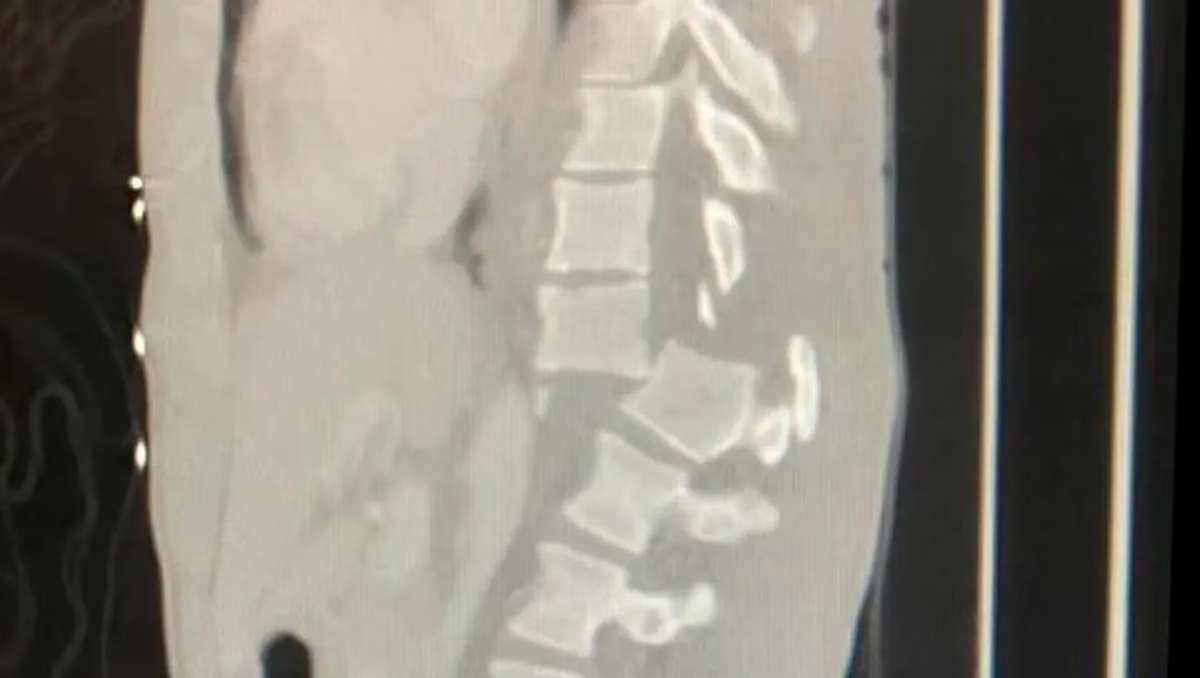

“Estaba en las piscinas naturales de Olivine y una gran ola me golpeó, me hizo desplomarme sobre las rocas. Me fracturé la columna y tuve que operarme de emergencia”, se puede leer en la solicitud.

Y concluyó: “Necesito regresar a mi país para iniciar mi rehabilitación lo antes posible. Necesito de tu ayuda para recaudar dinero y así poder cubrir los gastos del hospital y el vuelo médico hasta Argentina. Se los agradezco”.